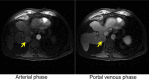

Hepatocellular carcinoma (HCC) is one of the most common tumors worldwide and one of the deadliest. Patients with chronic liver disease are at the highest risk for developing this tumor. This link provides an opportunity for developing preventive strategies and surveillance that aims at early detection of this tumor and possibly improving outcomes. In this review, we will discuss the latest developments in surveillance strategies, diagnosis, and treatment of this tumor. HCC is the sixth most common cancer in the world, with 782,000 new cases occurring in 2012 worldwide. In 2012, there were 746,000 deaths from liver cancer.1 HCC is the third most fatal cancer in the world.2 The distribution of HCC, which varies geographically, is related to the prevalence of hepatotropic virus. The burden of the disease is the highest in Eastern Asia, sub-Saharan Africa, and Melanesia where hepatitis B (HBV) infection is endemic. Meanwhile, in Japan, United States, and Europe, hepatitis C (HCV) infection is prevalent, and subsequently, is the major risk factor for acquiring HCC in these regions.1,3 It is estimated that the incidence of HCC in Europe and United States will peak at 2020-there will be 78,000 new HCC cases in Europe and 27,000 in the United States-and decline thereafter.1 Indeed, in Japan, the incidence of HCC had already plateaued and started to slowly fall.4 Cirrhosis is the most important risk factor for HCC regardless of etiology and may be caused by chronic viral hepatitis (mainly HBV and HCV), alcoholic liver disease, autoimmune disease, Stage 4 primary biliary cirrhosis, and metabolic diseases such as hereditary hemochromatosis, alpha-1 antitrypsin deficiency, and non-alcoholic fatty liver disease. In the Western hemisphere, HCC occurs in a background of cirrhosis in 90% of the cases.5 Before concentrating on diagnosis and therapeutics, it is important to discuss surveillance for this tumor.